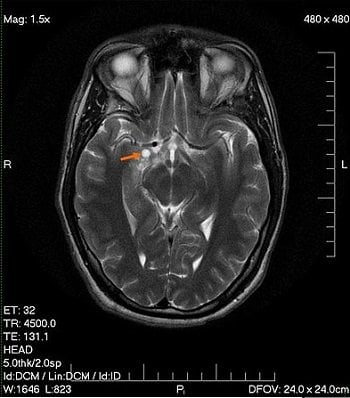

Image Source: The image is credited to Wikimedia Commons user Blondis and is in the public domain.